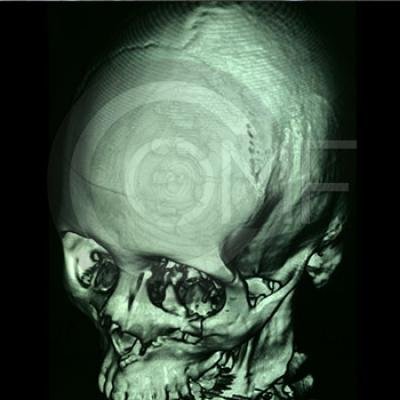

Fractura de Malar

Fractura De Malar14 Post